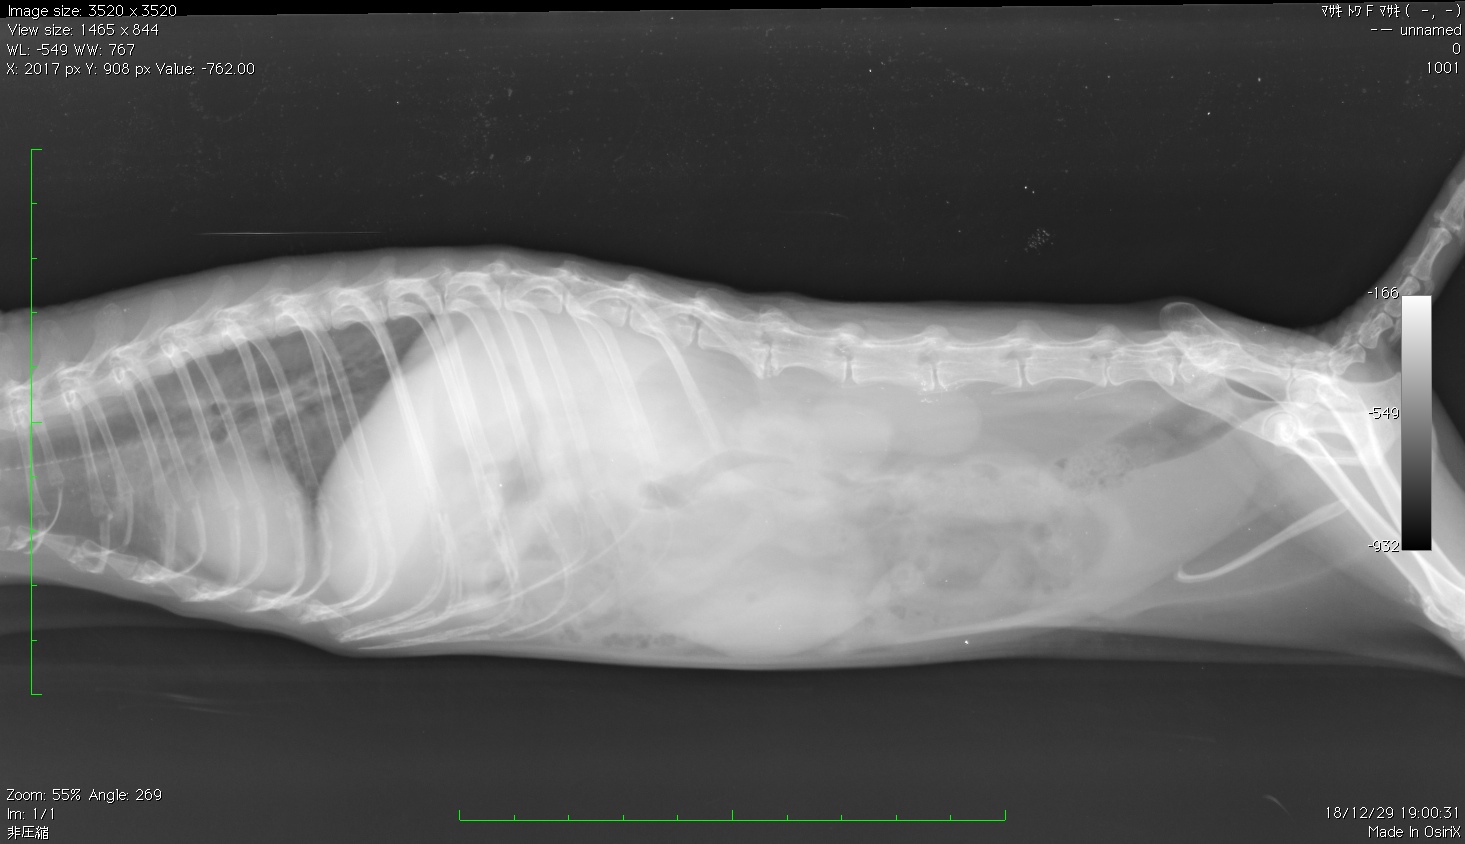

上記の図はデグーのチャコちゃんです。

後肢の効きが悪いで来院されました。

痛みはないのですが、歩行が上手にできなくなりました。

レントゲン画像で左が頭部・右が尻尾側・上が背中側となります。

その背中側中心部の脊椎部分の骨と骨が白くくっついています。

同じく確定診断にはMRIをとらないと分からないのですが、上記の永遠ちゃんと比べても

変形が著しく、臨床所見上、変形性脊椎症と判断しました。